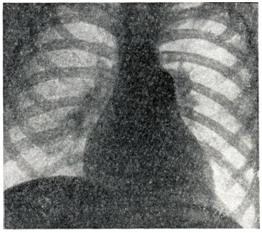

Рис. 1.

Расширение артериальных сосудов корней легких при синдроме Айерсы.

Рентгенологические признаки зависят от характера бронхо-легочного заболевания, а при его отсутствии соответствуют картине первичной легочной гипертензии. При рентгеноскопии видна усиленная пульсация легочного ствола и крупных ветвей легочной артерии и, как и на рентгенограммах (рис. 1.), определяются выбухание дуги легочного ствола, увеличение калибра артерий в корнях и прикорневых зонах легких, «ампутация» теней сегментарных сосудов и отсутствие легочного рисунка в периферических отделах легочных полей. В правом переднем косом положении отмечаются выбухание легочного конуса и увеличение диаметра круглой тени левой легочной артерии в ортогональной ее проекции. В левом переднем косом положении «аортальное окно» закрыто тенью расширенного легочного ствола; обычно, как и в боковом положении, имеются признаки увеличения правого желудочка.

Углубленное рентгенологическое исследование (томография, электрокимография, ангиокардиография) выявляет при Айерсы синдроме расширение только артериальных сосудов, в то время как легочные вены не расширены.